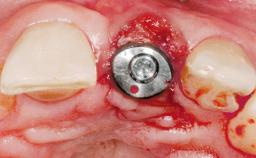

Immediate Flapless Placement of an Implant in a Maxillary Right Lateral Incisor Site

This 43-year-old male patient, a non-smoker, came to our practice because of a fracture of tooth 12 caused by a bicycle accident. Due to the combined para- and infrabony crown and root fracture, tooth extraction, and subsequent implant placement were suggested to the patient as the therapy of choice. The patient had high esthetic expectations with regard to the treatment outcome and asked for an immediate fixed provisional restoration. His individual esthetic risk profile summed up to a medium esthetic risk.

Placement Protocol Immediate implant placement

Tooth Site Maxillary incisor or canine

Loading Protocol Immediate

Retention Screw-retained Screw-retained